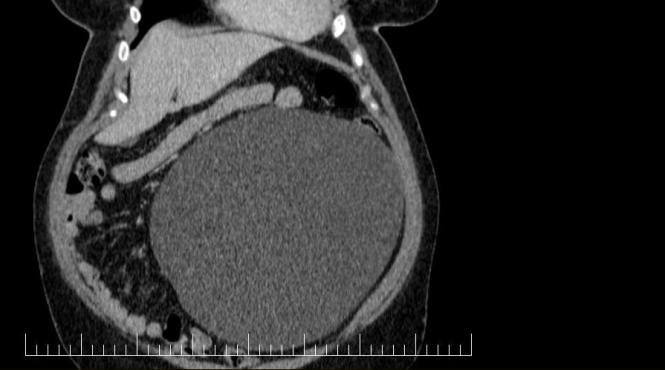

Performanță medicală la Sibiu: Chist ovarian de 4,5 kilograme, extirpat cu succes de la o pacientă